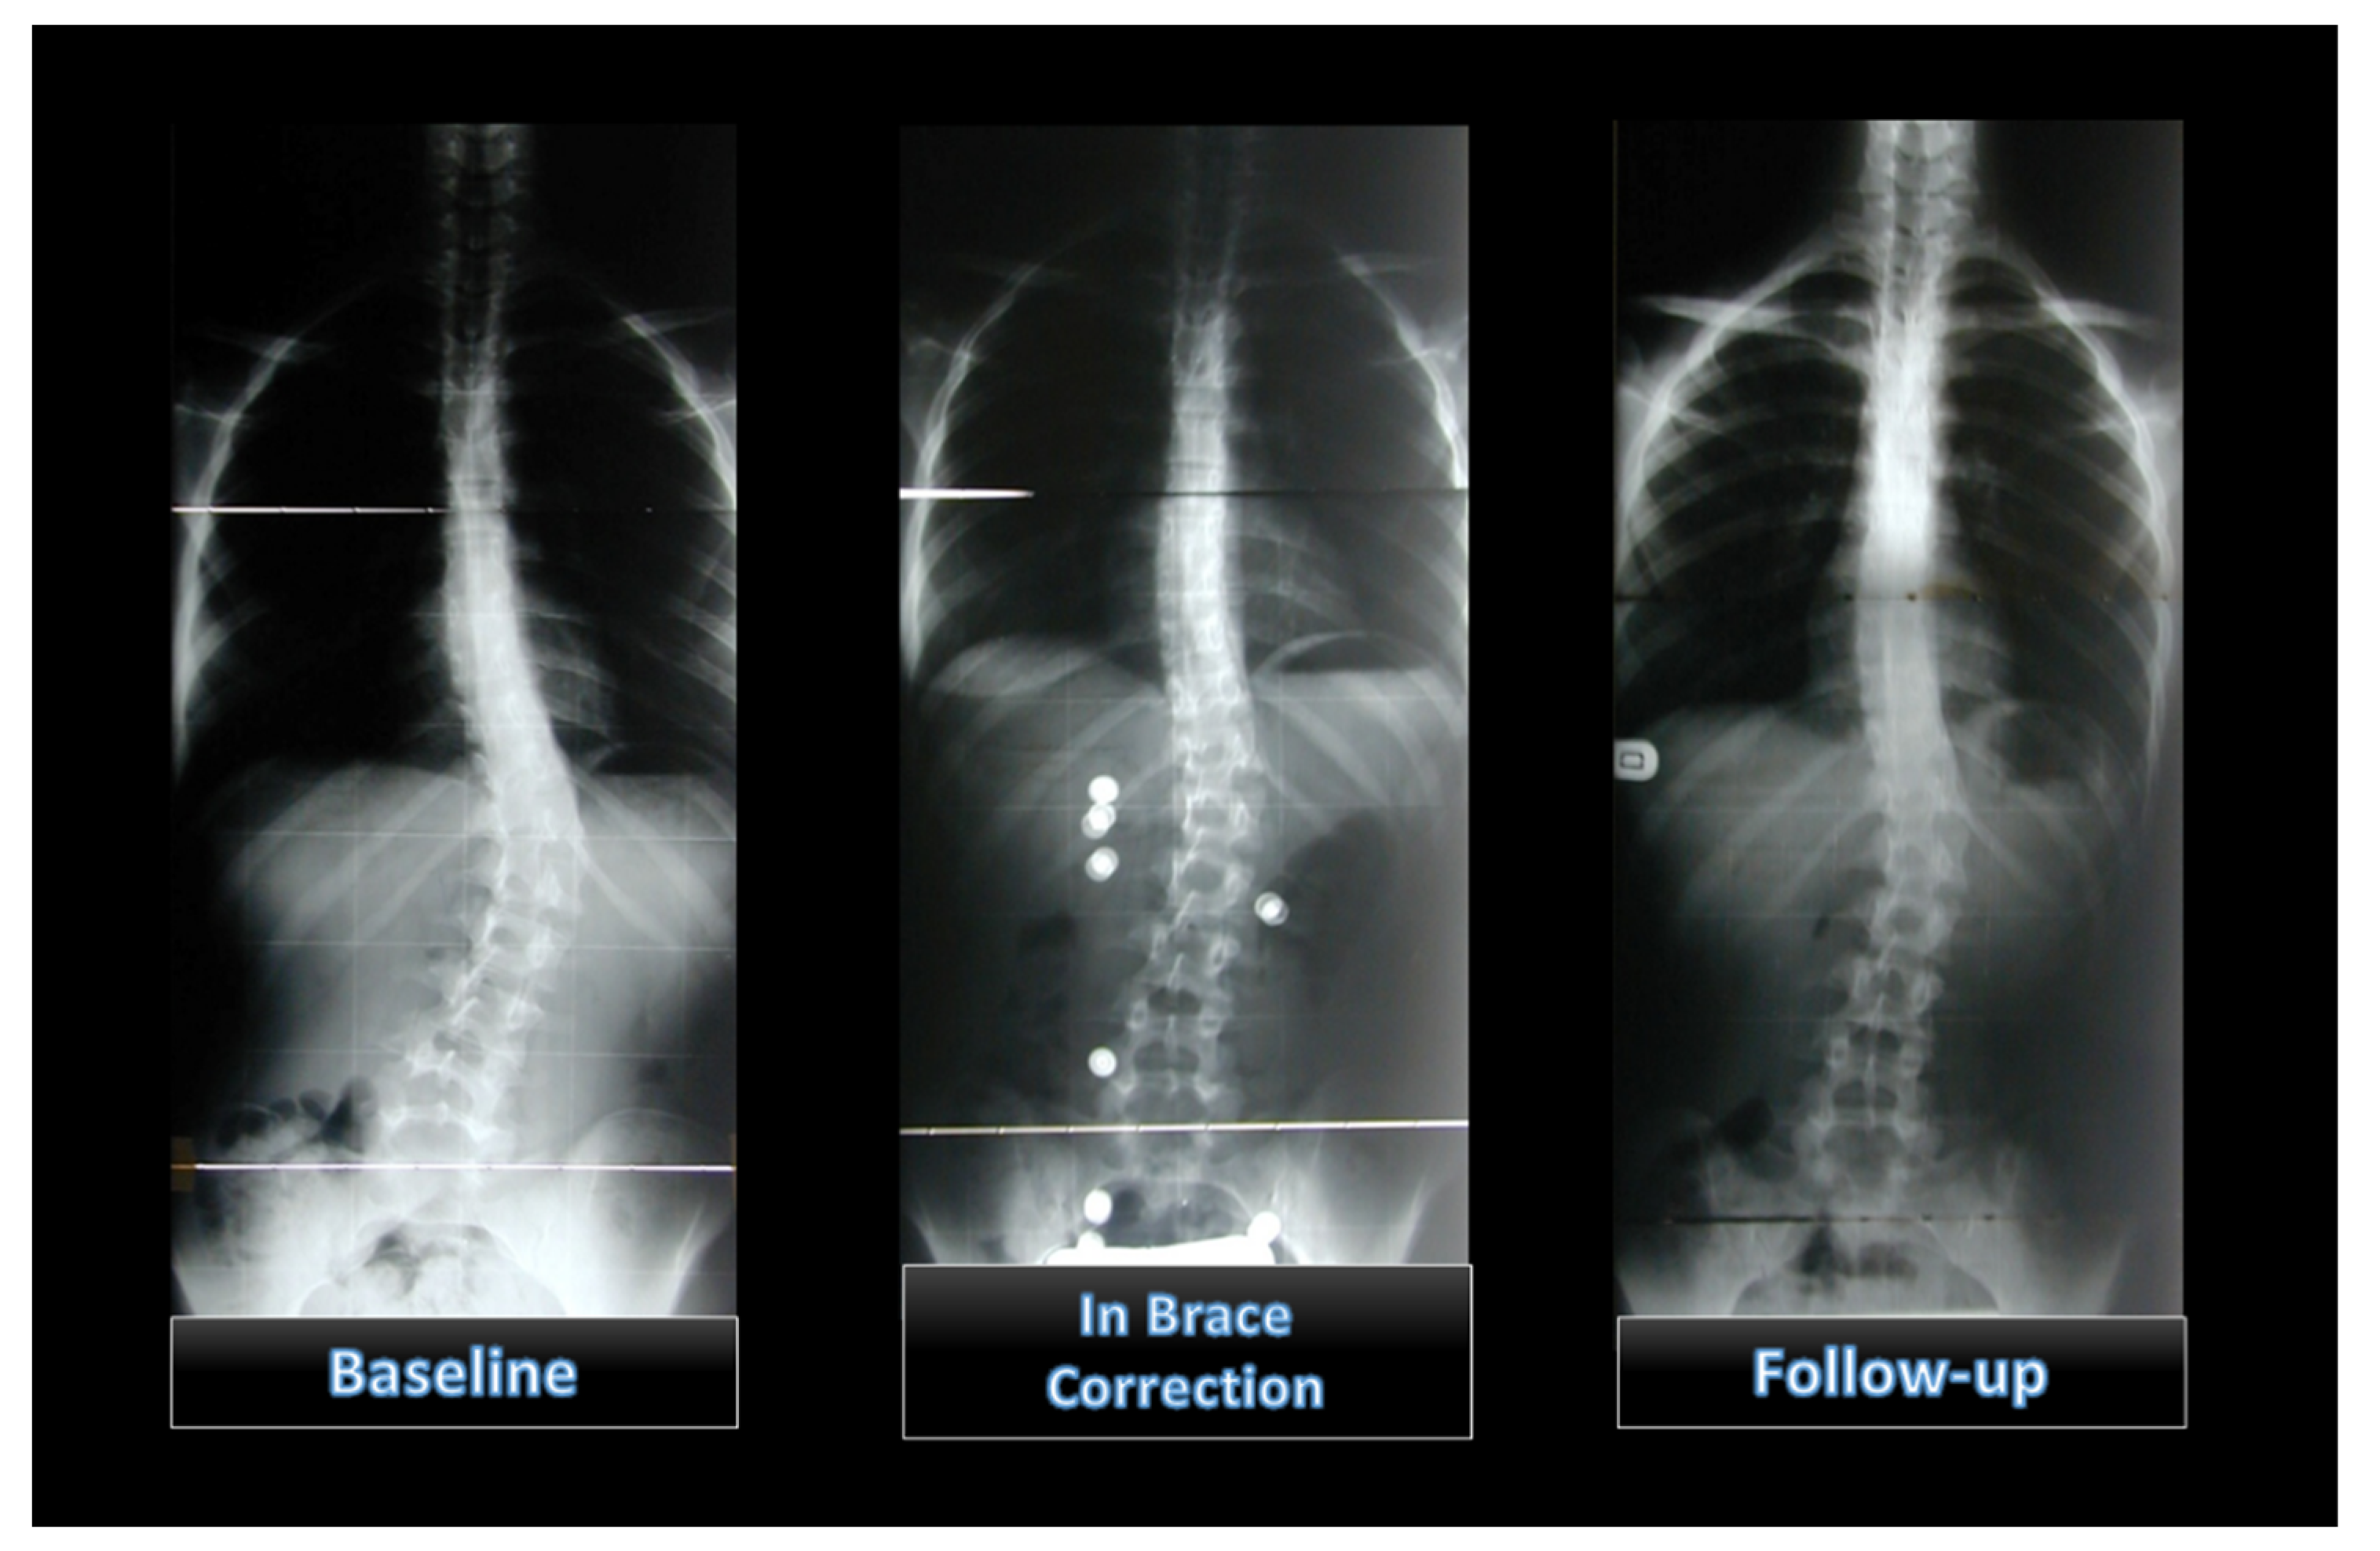

Initial In-Brace Correction: Can the Evaluation of Cobb Angle Be the Only Parameter Predictive of the Outcome of Brace Treatment in Patients with Adolescent Idiopathic Scoliosis?

2. Materials and Methods

2.1. Bracing Protocol

3. Results